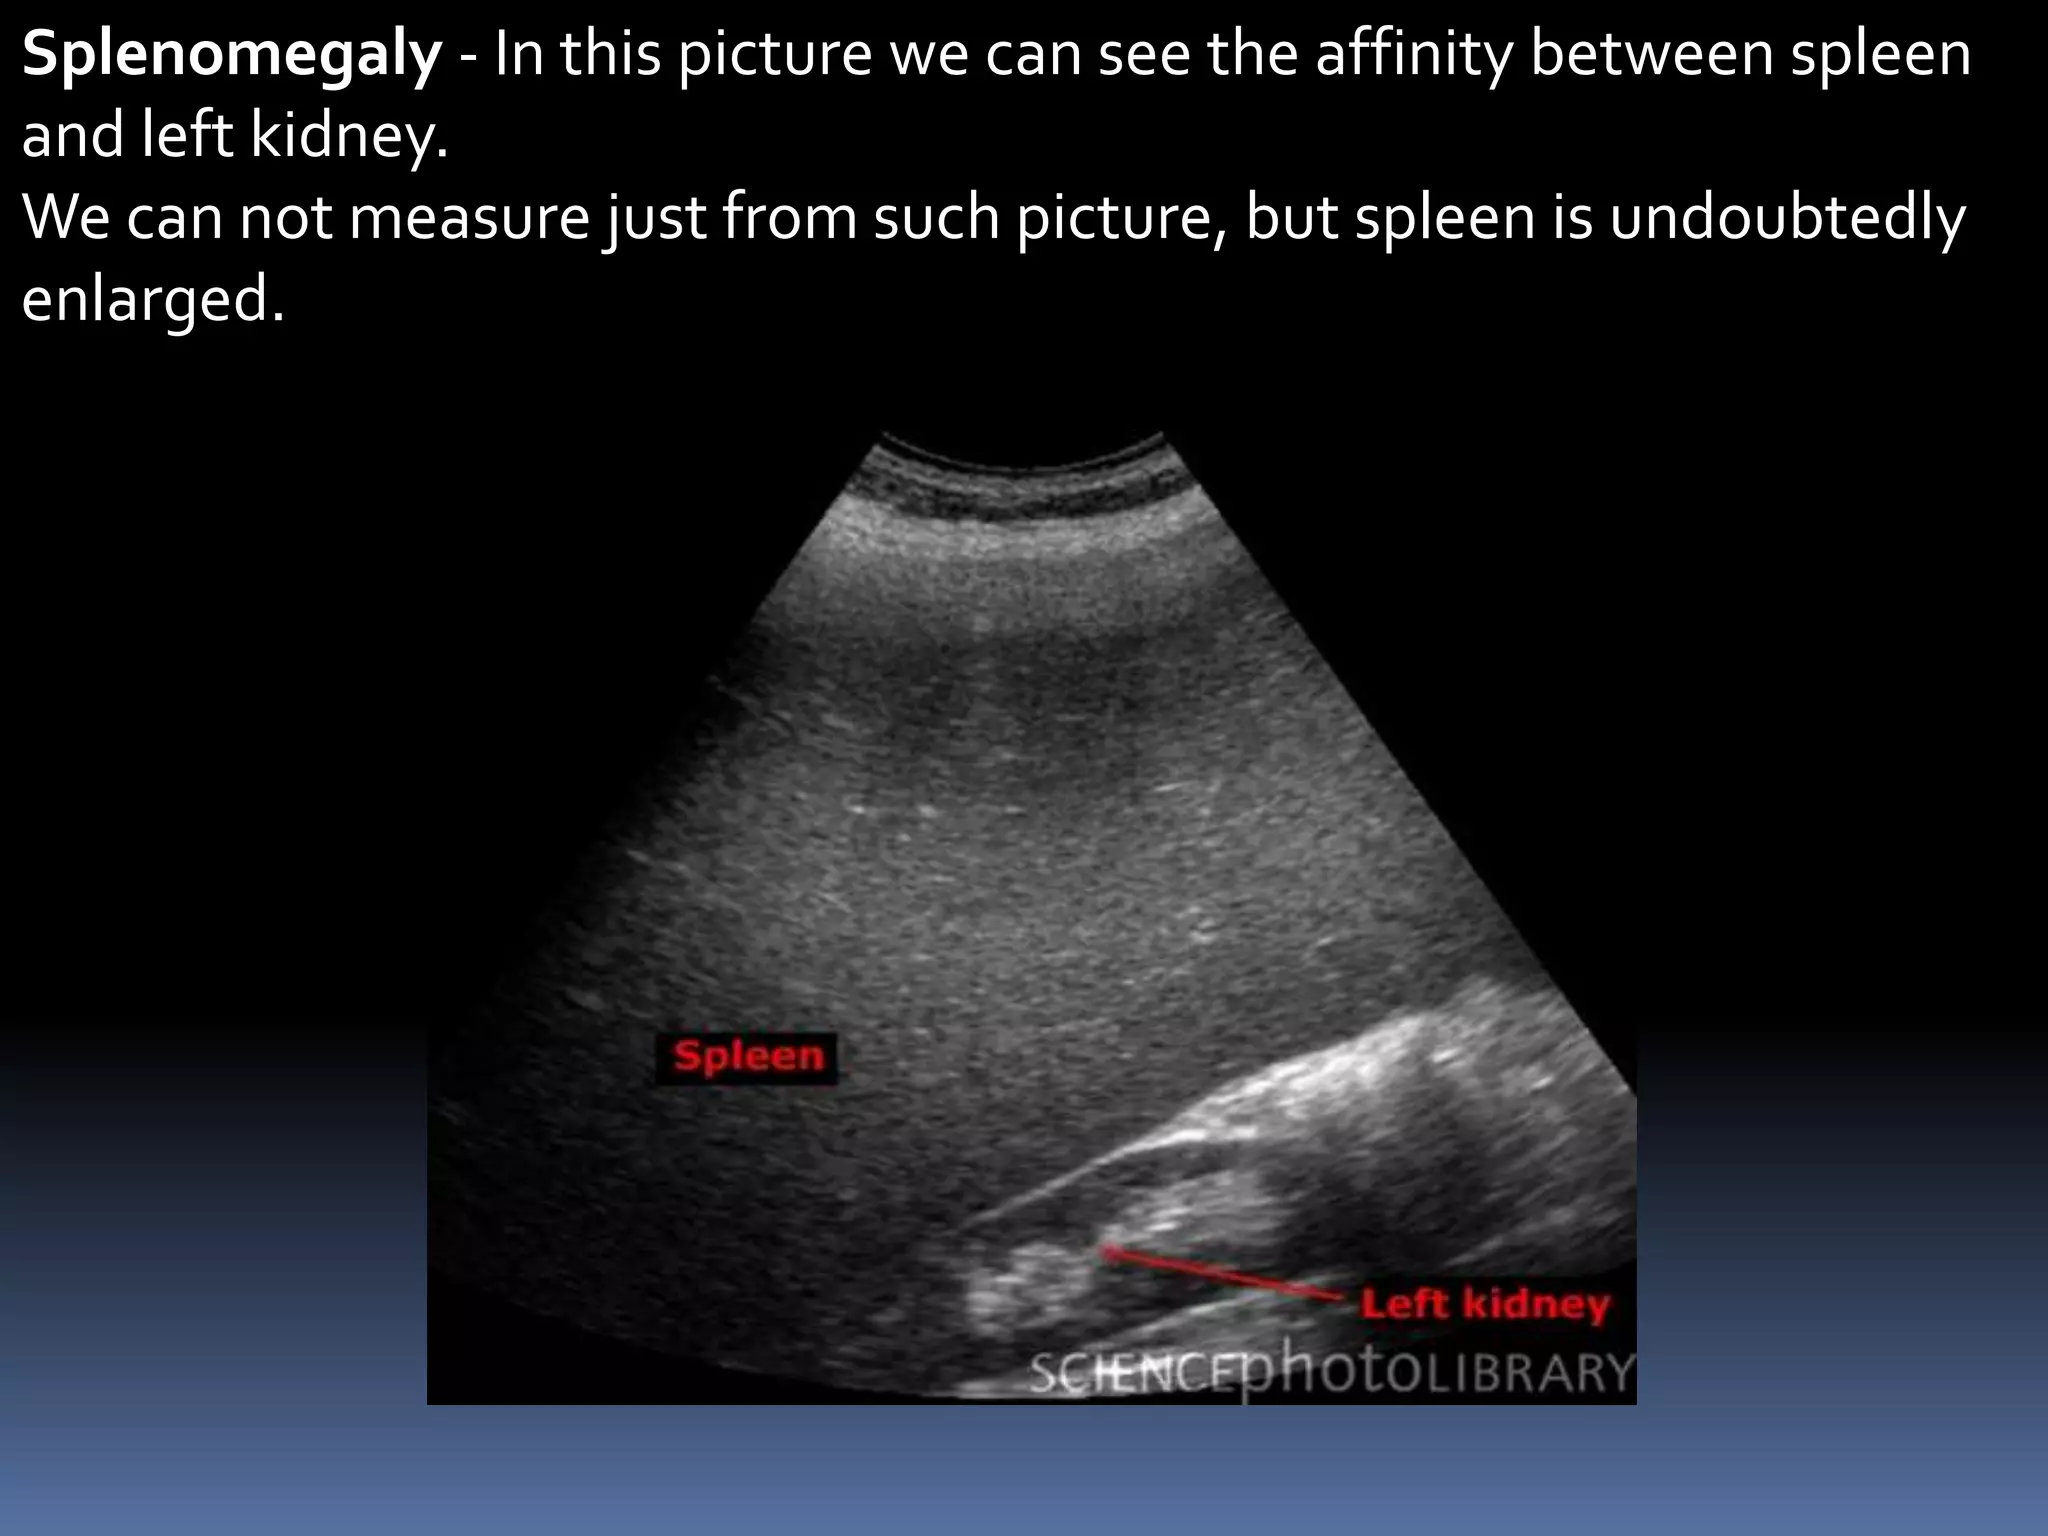

Splenomegaly - In this picture we can see the affinity between spleen

and left kidney.

We can not measure just from such picture, but spleen is undoubtedly

enlarged.